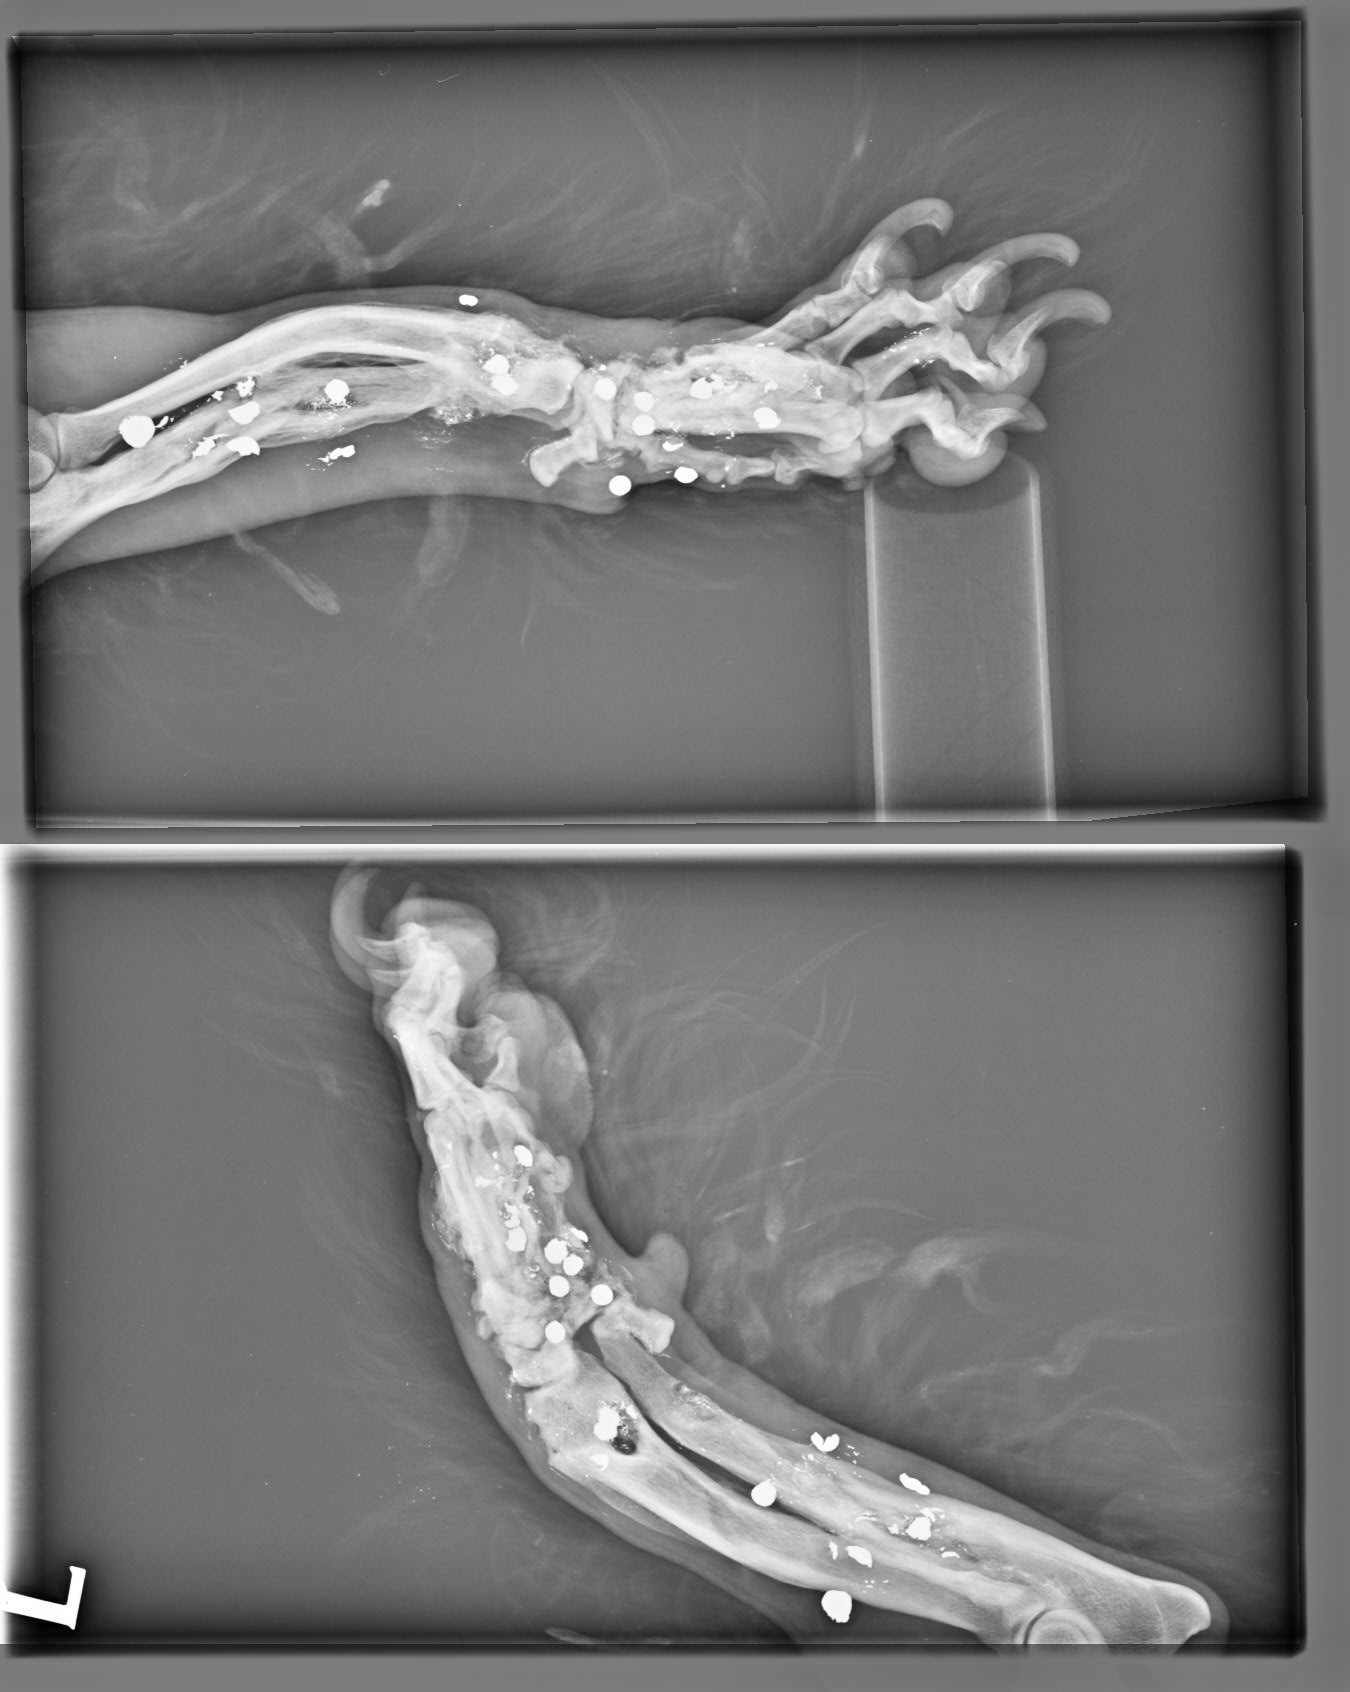

Brok, narodený marec 2019, sa našiel v obci Okoč. Krátko pred ním sa našiel veľmi podobný psík, do ktorého deti hádzali petardy. Brok žiaľ skončil horšie :( Celý je dostrieľaný, má v sebe kopu brokov, ktoré mu ale našťastie nevadia. Až na nožičku :( Tá je úplne dostieľaná, dolámaná a modlíme sa za zázrak, aby sa ešte dala zachrániť :( Brok ide na vyšetrenia, ktoré definitívne potvrdia či príde o nožičku, ale môže podstúpiť korekčné operácie, ktoré ale budú veľmi nákladné. Samozrejme do nového domova pôjde až po zákroku. Nožička ho našťastie vôbec nebolí, neprekáža mu, len trocha zavadzia, lebo ju nevie veľmi požívať :( Je to neskutočne tešívé, prítulné, veselé, spoločenské psíča, ktoré si hľadá aktívnu rodinu. Nie je vylúčené, že z neho bude trojnožka, ale na jeho povahe to nič nezmení :) Je znášanlivý, kontaktný, pozorný. Veľmi si užíva spoločnosť človeka, rád sa túli a mojká. Najspokojnejší je keď môže voľne behať vo výbehu. Na vodítku je trocha opatrný, ale to sa rýchlo doučí. Hľadáme mu rodinku, v ktorej bude plnohodnotným členom a nie ozdobou na záhrade. Je vhodný aj do bytu, ale bude treba doladiť prechádzky na vodítku a hygienické návyky. Ak ba sa mal adoptovať k rodinnému domu, tak výhradne s celoročným prístupom k svojej rodine. Brok čaká na svoju druhú šancu od marca 2020.